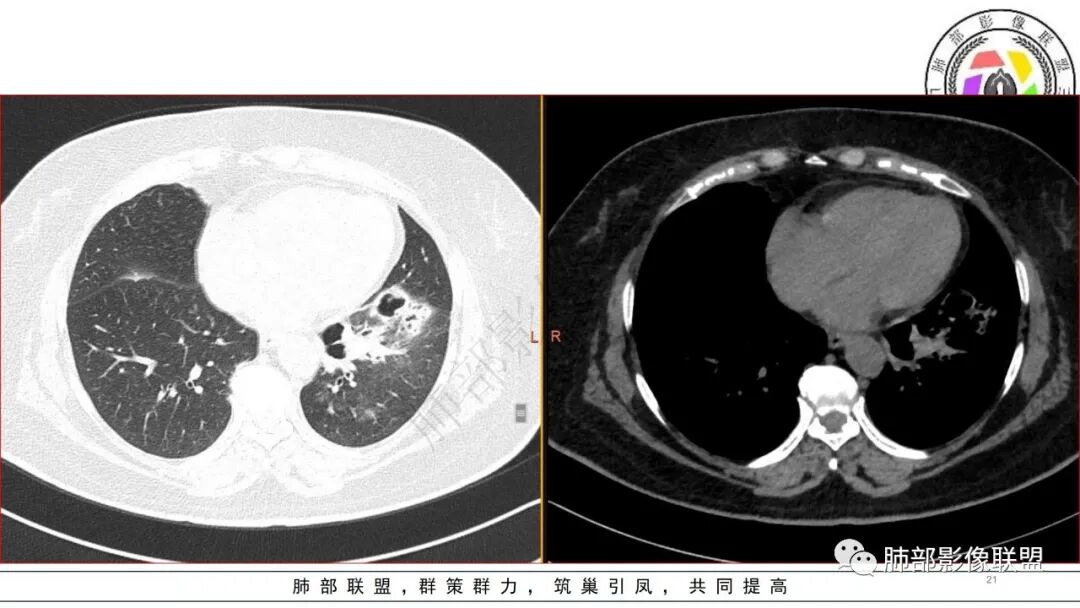

有糖尿病基层,左肺大片状实变影,跨多个叶段,多次治疗复查,实变范围有缩小,部分可见空洞影,考虑肺克

糖尿病,左下肺单侧实变,多次复查可见空洞和液平面,符合坏死性肺炎,白细胞高,遗憾的是不管是前期还是复查都没给PCT值,有手术史,首先考虑肺克,鉴别金葡和大肠埃希菌

糖尿病基础,左下肺感染性病变,进展快,先是左肺大片实变,短时间复查出现空洞,治疗两周周边有吸收好转,空洞壁变薄。金毛结克,我倾向金葡菌。鉴别肺克。

老年患者,糖尿病病史14年,不规律降糖治疗,血糖控制不佳,咳嗽、喘息两天就诊,查血常规白细胞轻度升高,CRP显著升高,首诊CT提示左下基底大片实变,边界不清,周围播散灶,短期复查病灶呈吸收好转趋势,并出现多发空洞,空洞形态不规则,病灶内未见气液平,考虑感染性病变:

女,61,糖尿病史,CRP、血像、ESR、CA199等增高,白蛋白低。胸部CT:左下肺大片实变影,边缘模糊,短期复查部分吸收,多发空洞形成,成簇,大小不等,无液平。考虑,金葡?肺克?奴卡?鉴别支扩伴感染、CPAM等。

老年女性,有14年糖尿病史,咳嗽、喘息2天。白细胞计数稍升高。1.13CT:左下肺大片实变,经抗感染治疗,短期变为多发气囊及空洞样病灶。病灶考虑气道来源,短期变化大,不支持肺结核诊断;无咯血症状,短时间内变化大,毛霉可能性小;肺克及金葡感染难以鉴别,建议完善降钙素原检查进一步判断。个人倾向于肺克。

短期内变化明显,左下肺随治疗进展可见气囊影,实变内可见空洞及支扩,考虑炎性感染性病变,病史较短,变化较大,可排除丅B及奴卡,无咳血可排除毛霉,综和考虑金葡>肺克,其次要考虑合并铜绿感染的可能

2.左肺下叶大范围实性密度影,散乱,边界不清,可见液化空洞,病变肺体积轻度增大。支气管相关(相应支气管闭塞)。

3.五天后及十三天后病灶变化明显,实性密度影吸收缩小,边界趋于清楚,显示多空腔。

1.局限于单肺叶的大范围实性密度影,边界不清,看不出外壁的液化空洞,多符合化脓性感染。

3.金黄色葡萄球菌临床中毒症状明显,常寒颤高热起病,血源性感染者常有皮肤脓肿、伤口感染、蜂窝织炎、化脓性骨髓炎等等。病情变化快,影像进展迅速,短期内(如一两天内)迅速出现的有张力的菲薄气囊影,或多发成串分布的,尤具特征性!较之其他感染,短期内易出现脓胸。本例上述特征似乎不明显。

4.肺炎克雷伯杆菌肺炎病灶也易形成脓腔。本例患者未出现典型金葡感染影像学特征,患者临床表现相对“逍遥”缓慢,结合实验室检查,更符合肺炎克雷伯杆菌肺炎。